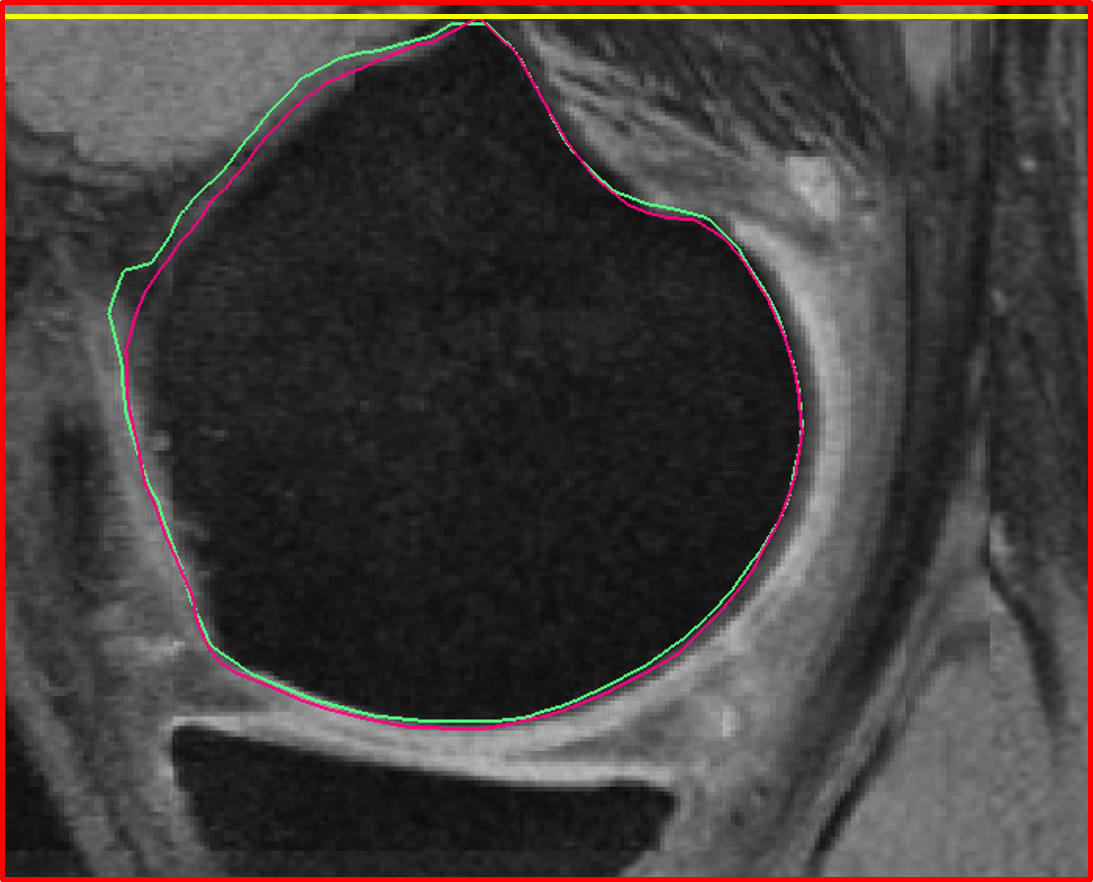

Fig. 7 qualitatively compares the segmentation accuracies between the gradient-based costs and the hierarchical classifier with respect to the independent standard. Both the femur and tibia are shown with their respective bone and cartilage segmentations showing good agreement between learning-based segmentation and the independent standard.

Fig. 8 qualitatively shows the improvement of 4D LOGISMOS over 3D. Note the lack of an obvious edge distinguishing the tibia and femur cartilage. Using the spatial and temporal contextual information from all the time-points, the 4D method is able to correctly position the cartilage for the tibia and femur despite the lack of image information locally.